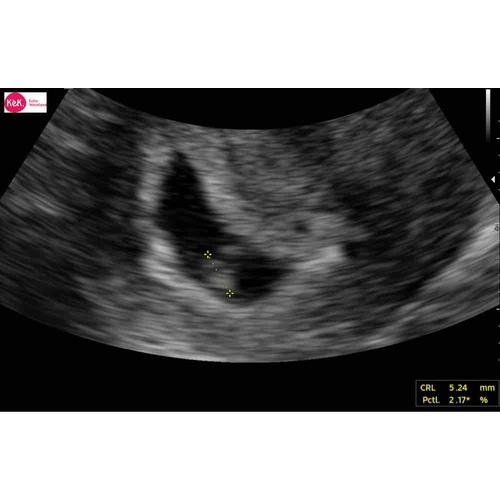

Hoi allen, hoe is het uiteindelijk bij jullie allemaal verlopen? Wij hadden gister onze eerste echo (ongeveer 6.3 wk) en onze Vk was ook wat voorzichtig met goed nieuws brengen door de vorm van de vruchtzak. Echter wel een hartslag; langzaam maar dit hoeft nog niets te betekenen met dit termijn.